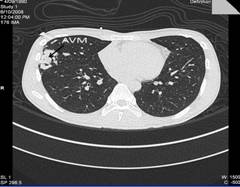

Complete blood count revealed polycythaemia (Hb of 210 g/L; HCT 0.64 L/L). Computed Tomography (CT) brain showed evidence of a right pontine infarct with no suggestion of cerebral arteriovenous malformation. Chest radiograph showed a faint right mid-zone opacity. Transthoracic echocardiography showed no evidence of septal wall defects or large vessel anomalies and no pulmonary hypertension. Plain CT of the chest suggested the presence of a PAVM (Figure 1). This was confirmed by CT pulmonary angiogram which revealed a solitary PAVM with two feeder vessels in the lower lobe of the right lung (Figure 2 and 3).

Figure 3: 3-D reconstruction of CT pulmonary angiogram shows in greater detail the AVM with feeder vessels from the right pulmonary artery (PA). PV: pulmonary vein; AVM: arteriovenous malformation; RA: right atrium.